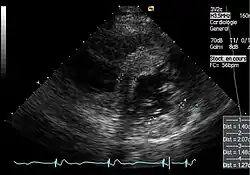

Die linksventrikulären strukturellen Veränderungen des Herzens finden sich bei Morbus-Fabry-Patienten häufig. Mittels Echokardiografie (Ultraschalluntersuchung des Herzens) oder kardialer Magnetresonanztomographie (MRT) können die meist konzentrischen Hypertrophien[80][81] sichtbar gemacht werden. Da mit zunehmendem Alter durch die Ersatzfibrose die linksventrikuläre Hinterwand des Herzens immer dünner wird, ist die Messung der Septumdicke – das ist die Stärke der Scheidewand zwischen linker und rechter Herzhälfte – besonders wichtig. Unabhängig von den strukturellen Veränderungen scheint die Systole, die Phase, in der das Blut aus der linken und rechten Herzkammer herausgepresst wird, bei der Messung mit konventionellen Methoden weitgehend erhalten zu bleiben.[80][81][82][91] Die durch Morbus Fabry verursachte Kardiomyopathie ist durch eine reduzierte Kontraktion und Relaxation des Herzmuskels gekennzeichnet. Gewebedoppler (sowohl tissue velocity imaging als auch strain rate imaging) kann die Herzmuskelfunktion quantifizieren.[7][92] Mit dieser Methode kann die Kardiomyopathie noch vor der Entwicklung einer linksventrikulären Hypertrophie diagnostiziert werden.[91][93]

- Echokardiografien von Patienten mit Morbus Fabry

Parasternale lange Achse: Deutlich sichtbar die linksventrikuläre Hypertrophie mit erhöhter Septumdicke. -

Parasternale kurze Achse: Die Aufnahme zeigt ebenfalls eine linksventrikuläre Hypertrophie. -

Gewebedoppler-Echokardiographie des Mitralanulus (Mitralring) mit nahezu normaler systolischer Funktion